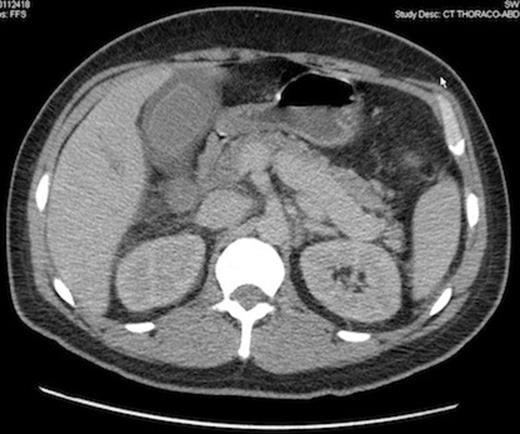

Computed tomography scan showing peritoneal bleeding from hepatic laceration after gallbladder percutaneous transhepatic drainage.

The patient was considered to unstable for a surgical intervention and an emergency percutaneous CT-guided cholecystostomy was done, in spite of a very low platelet count (7 000/mm3). 24 hours later, the septic shock rapidly improved, but hemoglobin level fell down from 83 to 61 g/L. A CT scan showed a bleeding liver laceration with intraperitoneal haemorrhage secondary to the transhepatic percutaneous gallbladder drainage.